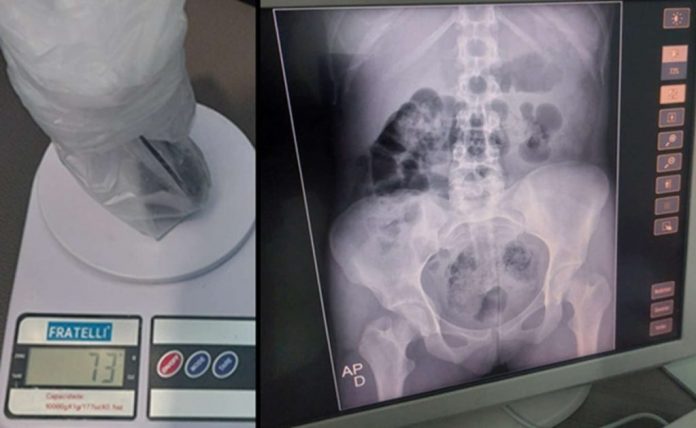

De acordo com a direção do presídio, uma das mulheres carregava dois pacotes nas partes íntimas, sendo um deles 50 gramas de maconha e o outro com um pouco mais de 50 gramas de cocaína.

As mulheres foram levadas para o Hospital Regional de Cajazeiras (HRC) para retirada dos entorpecentes. Uma delas deve ser submetida a um procedimento cirúrgico devido ao volume considerável de drogas.